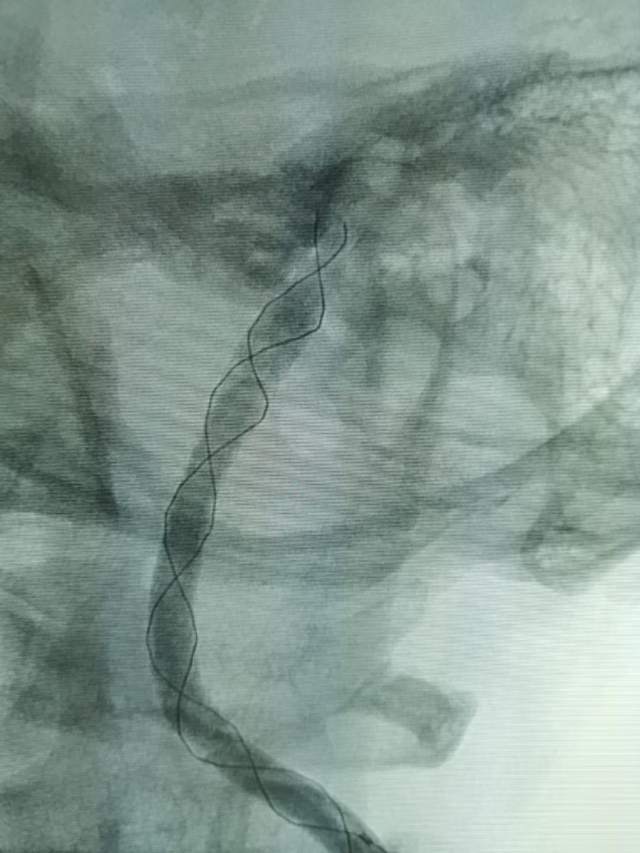

遗留右侧肢体残疾,尽管卧床康复3个月,肢体也只能在床上平移,无法抬离床面,完全性失语,不能说话。家属老爸经人介绍辗转收入我科,看看能否得到进一步的改善。第一次晨间病房查房,看到纯朴、善良、苍老的老爸站在床边,向我们不紧不慢的诉说着女儿的病情,年轻秀丽的女儿静静躺在床上,一言不发(完全性失语),想到独生子女家庭在老年突然遭遇失独、残疾等意外后,本是年轻人照顾老年人的季节,现如今却成了白发人弓着背照顾残疾的黑发人,让人心中一阵苍凉和心酸。患者左侧大面积脑梗塞三个月,右侧肢体肌力只有2级,完全性失语;左侧大脑前动脉向左侧大脑中动脉代偿供血,基于上述情况,可能能够做的外科工作并不多,进一步康复的希望也不大。尽管如此,我们还是认真的对患者进行了详尽细致的评估,看看能否找到突破点。造影发现患者颈内动脉起始部存在颈动脉蹼(可能是三个月前引起梗塞的原因,图3)

还有两处隐约可见的颈动脉夹层,造影期间血管局部构型短时间内出现改变,提示夹层影响远端血流,修复夹层对患者至关重要

于是一个支架重建两处夹层和颈动脉蹼(花钱少,一个支架解决3个病变),手术顺利。